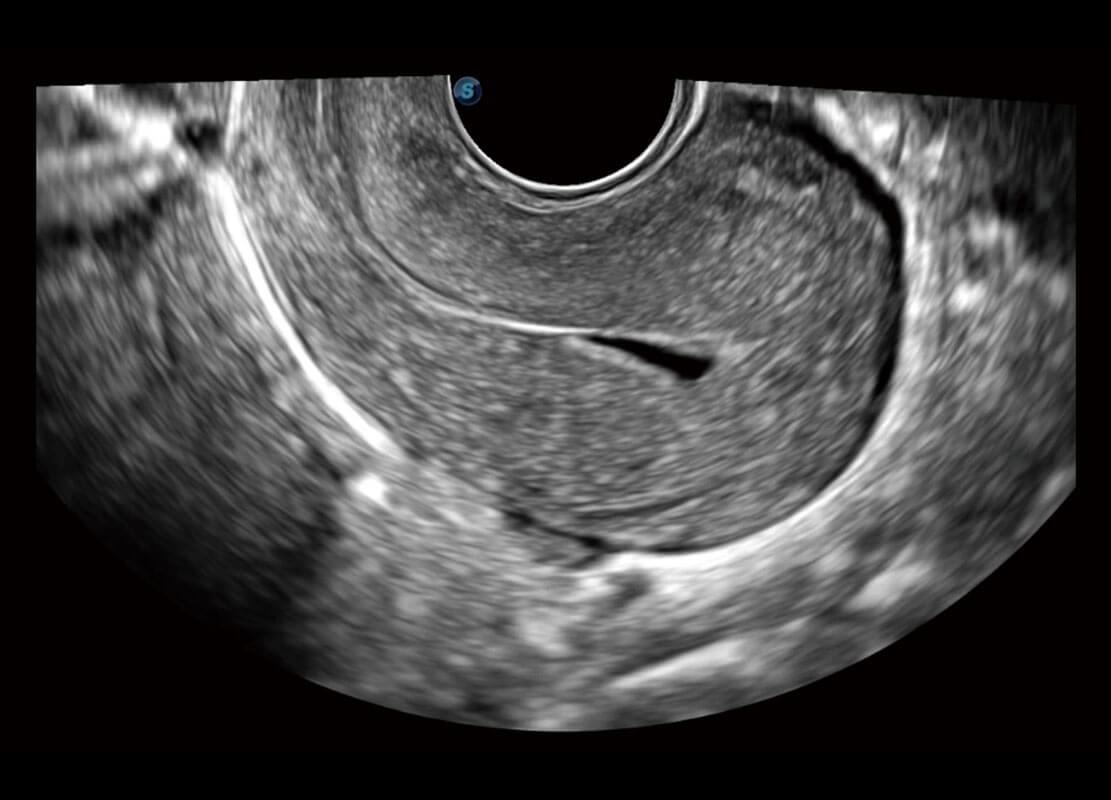

腔内妇科-宫腔分离

腔内妇科-卵巢

腔内三维-宫内节育器

腔内三维-光影成像

P60优异的图像质量搭载专科探头,在妇科基础疾病的诊断、卵泡生长的监测、输卵管通畅情况的判别等方面为您提供生殖应用方案。